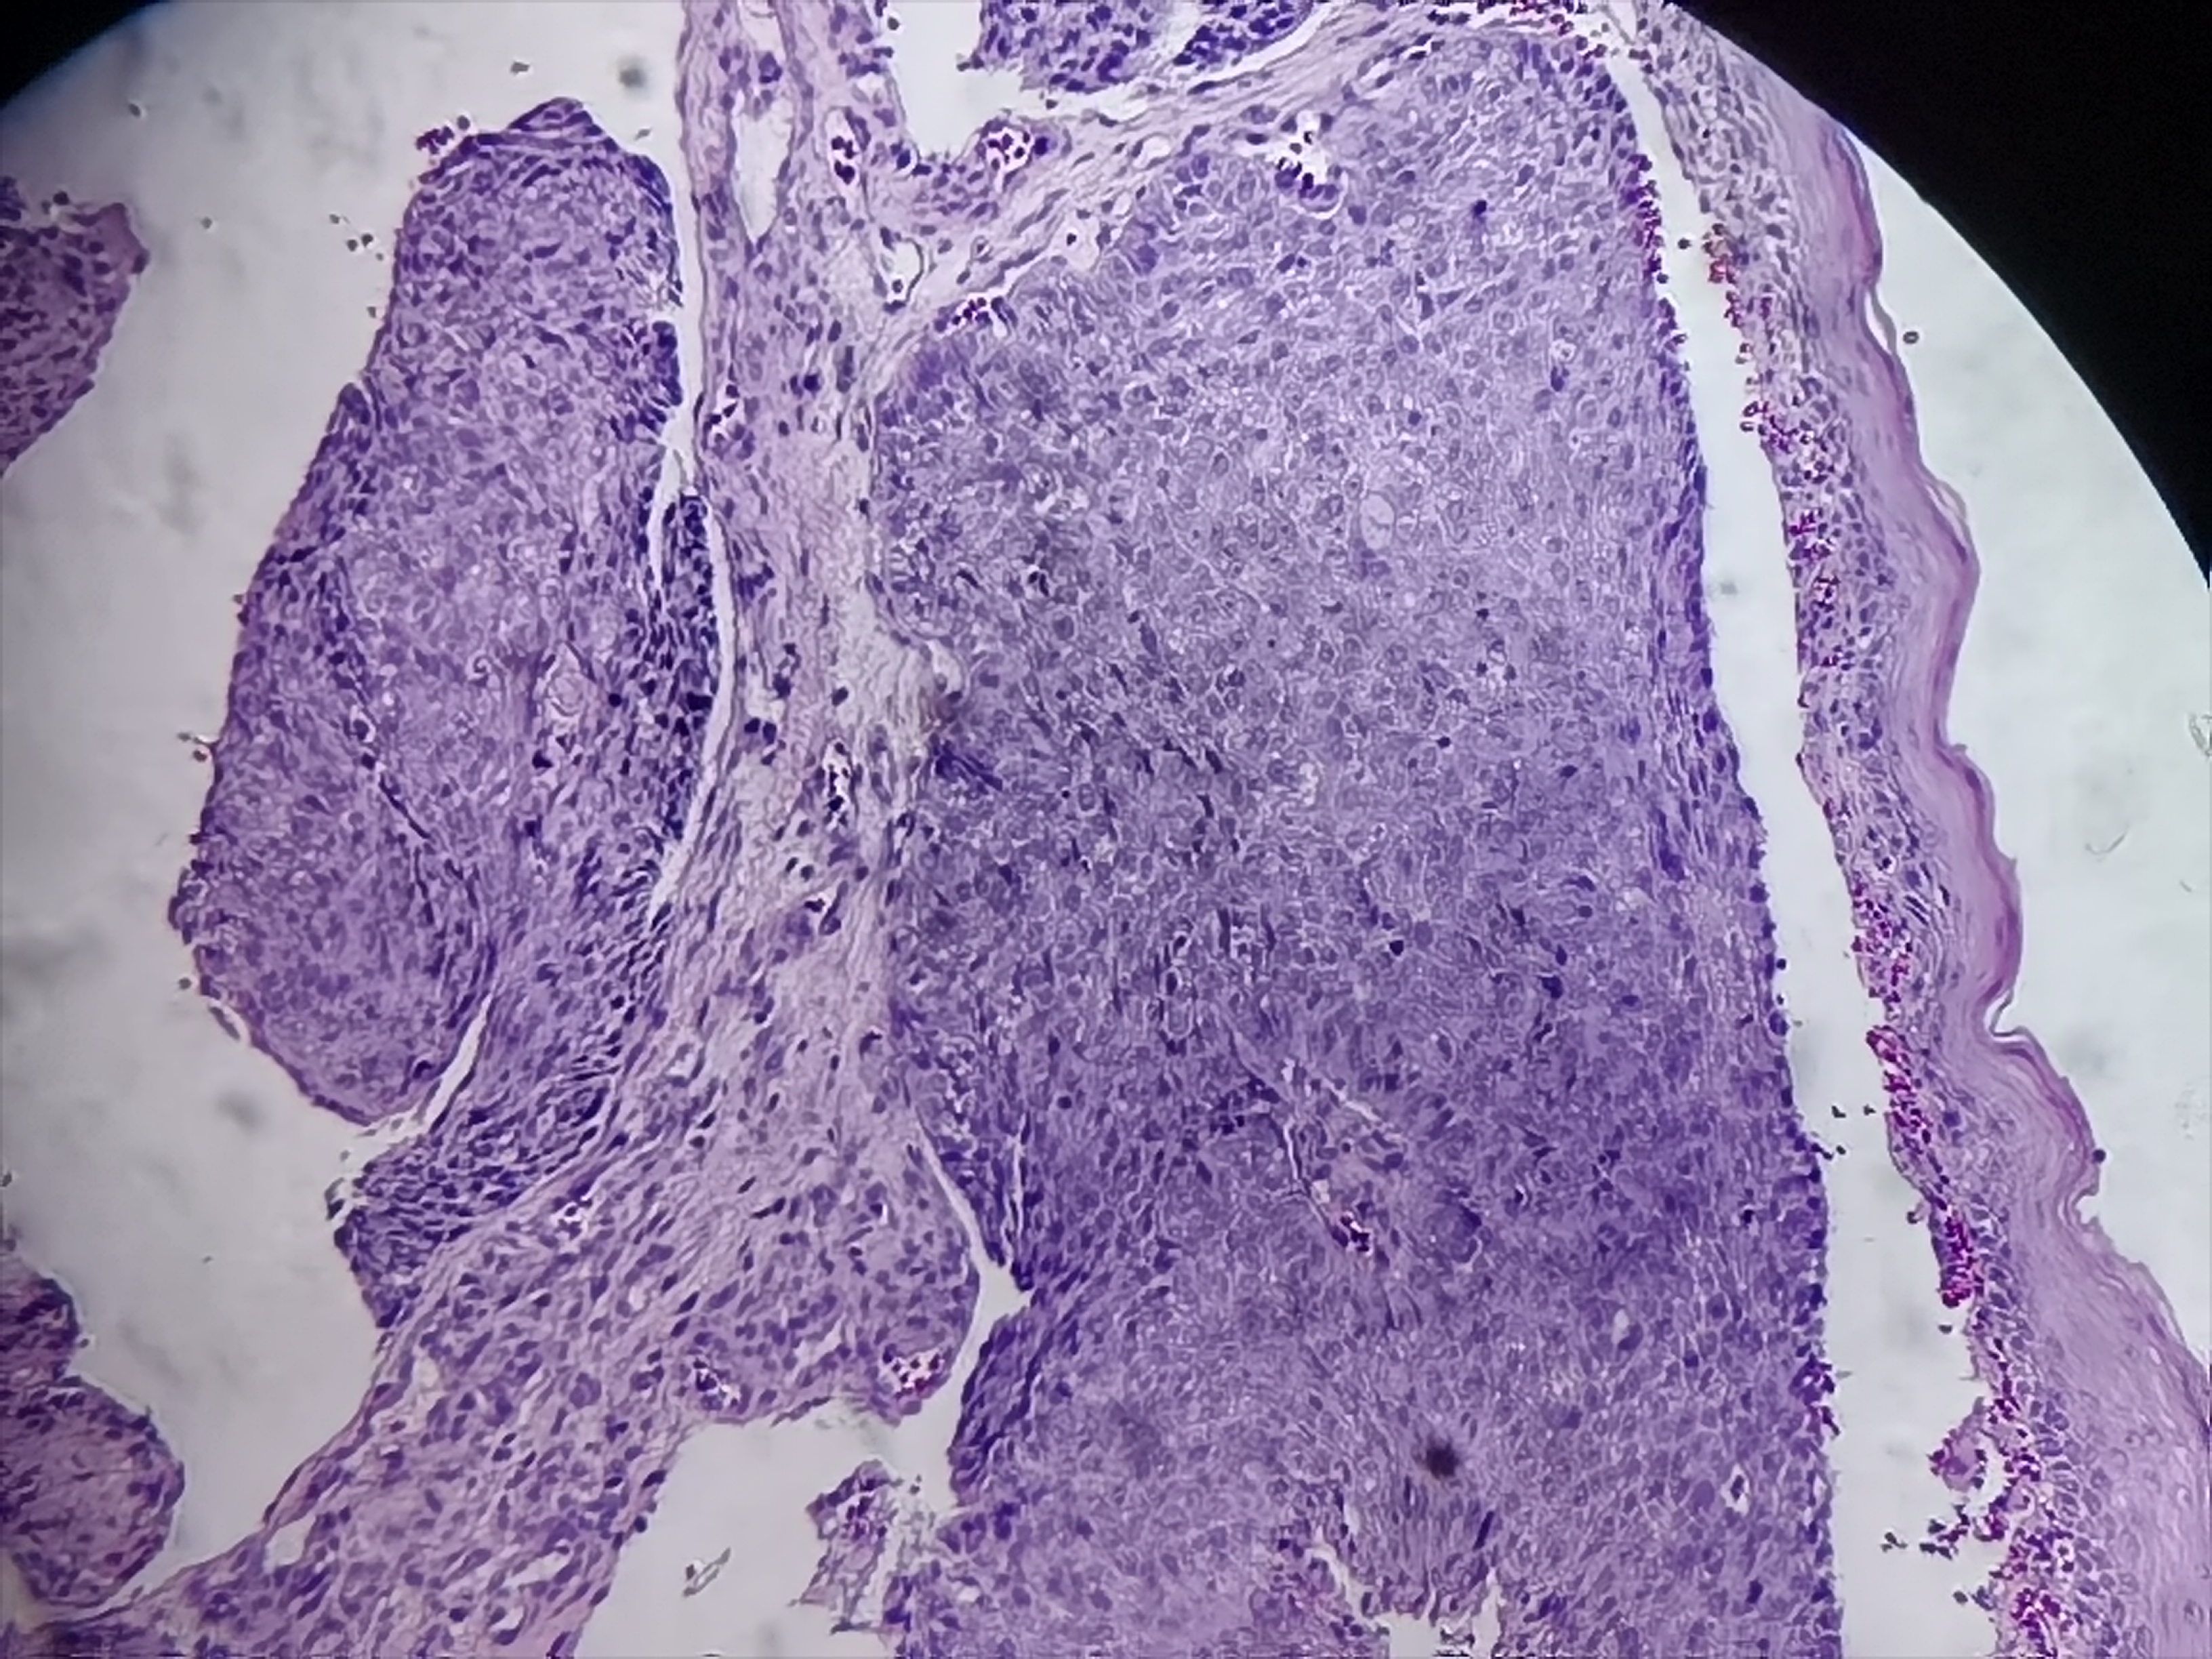

食管活检

性别

男

年龄

60岁

食管:距门齿21-27cm处可见不规则病灶

食管粘膜活检

灰白色组织4块

请教各位老师

图1

SCC..